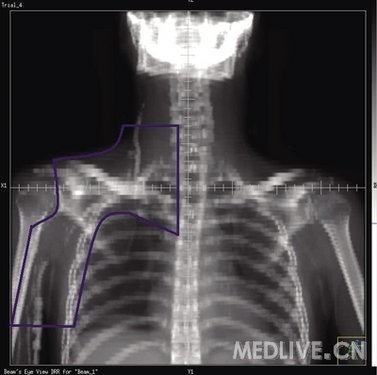

3 单颈纵隔野

肿瘤侵犯范围:纵隔淋巴结±肺门淋巴结和一侧颈部淋巴结。

靶区定义:纵隔、双侧肺门和一侧颈部区域,未包括耳前区(图3)。

上界:同侧上界为下颌骨体中线和乳突尖或耳垂连线,对侧上界位于颈6锥体上缘。

下界:隆突下5 cm或胸8椎体下缘或化疗前肿瘤下界下2 cm。

内界:颈部为体中线,保护未受侵一侧的上颈部。

外界:体中线左右各旁开4~5 cm,双锁骨上外界为肱骨头内缘。

肺门:包括1 cm边缘,若肺门受侵,包括1.5 cm边缘。